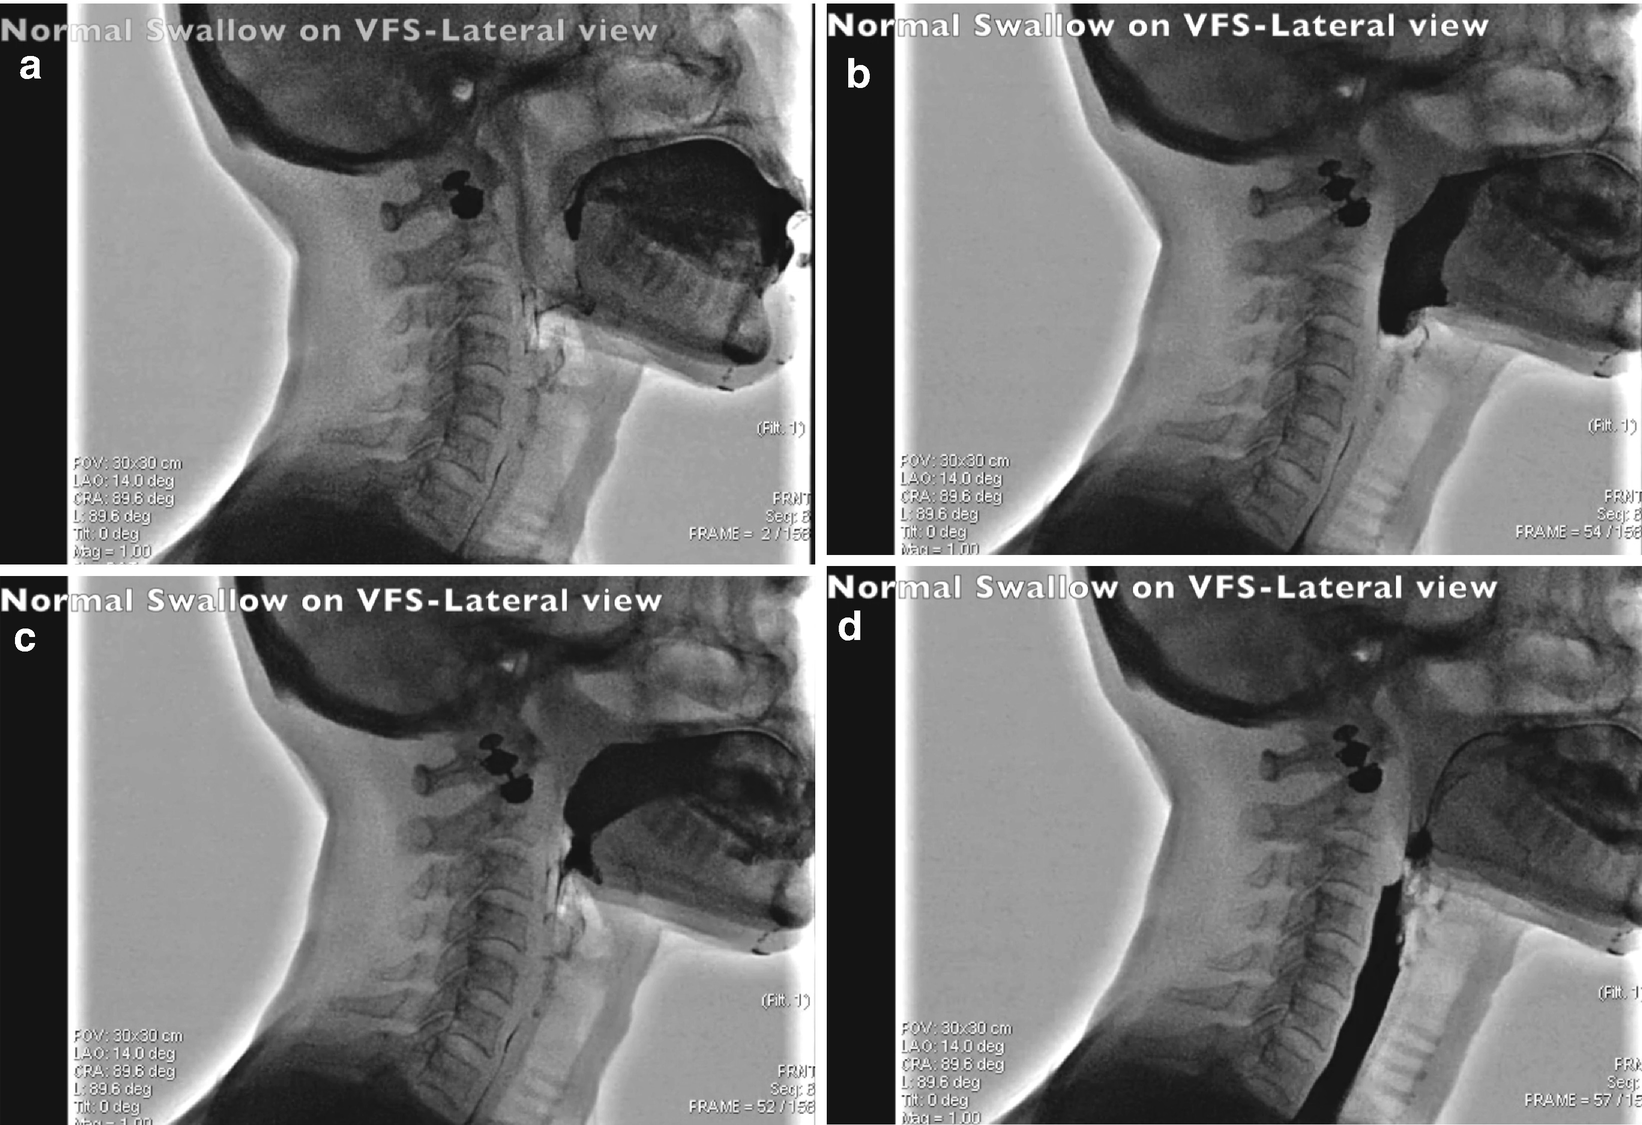

What causes residue in the vallecula. Where large quantities of valleculae residue exist the individual is at increased risk of aspirating residue during respiration after swallowing. Videofluoroscopic swallow studies have demonstrated that when there is insufficient contact between base tongue and posterior pharyngeal wall residue remains in the valleculae 26. Patients with deviant epiglottic function were more likely to have oral involvement reduced hyoid elevation or vallecular residue than patients without deviant epiglottic function and patients with reduced hyoid elevation were more likely to have oral involvement than those with normal hyoid elevation.

If we see that the pharyngeal swallow occurs but very little enters the esophagus and there is residue in the pyriforms what do we suspect. Reduced laryngeal elevation and anterior movement causing reduced cricopharyngeal opening UES - If no reduced laryngeal elevation could be reduced relaxation of the UES. Vallecula is present between epiglottis and base of tongue.

Very good to excellent for inter-rater reliability for vallecula kappa 0868 0011 and pyriform sinus kappa 0751 0011. And excellent for validity for vallecula kappa 0951 0014 and pyriform sinus kappa 0908 0017. We assessed 6 parameters for the diagnosis of dysphagia by FEES and VFSS.

2 delay in initiation of swallowing. 3 residue of the bolus in the oropharynx after swallowing. 4 residue of the bolus in the hypopharynx after at least 3 swallows ie saliva secretions or swallowed materials contrast-enhanced in VFSS accumulated in the valleculae on the lateral or posterior pharyngeal walls or in the piriform sinuses after deglutition.